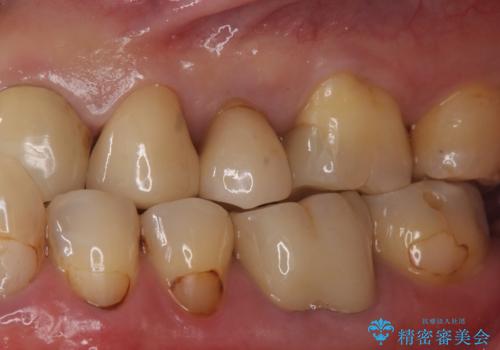

- 銀の詰め物をやりかえたい。とのことで来院。

白い物を希望されたので、以下の提案を行い選んで頂いた。

①セラミックインレーにやりかえ

噛む面は白くなり、歯質を多く削らなくてすむが、

表面の黒いところまでは覆えない。

②ジルコニアクラウンで被せる

表面の黒いところまで覆う事ができる。

ただし、①よりも歯を大きく削ることになる。

患者様と相談し、黒いところも目立たなくしたいとのご希望だった。

そのため、歯質の削除量は増えるが、クラウンで被せる②の方針で行うことになった。

歯の表面の黒いところは虫歯ではなく

歯ブラシによる摩耗か歯ぎしりによるくさび状欠損によるものです。

そのままだと水などが染みてくる原因にもなります。